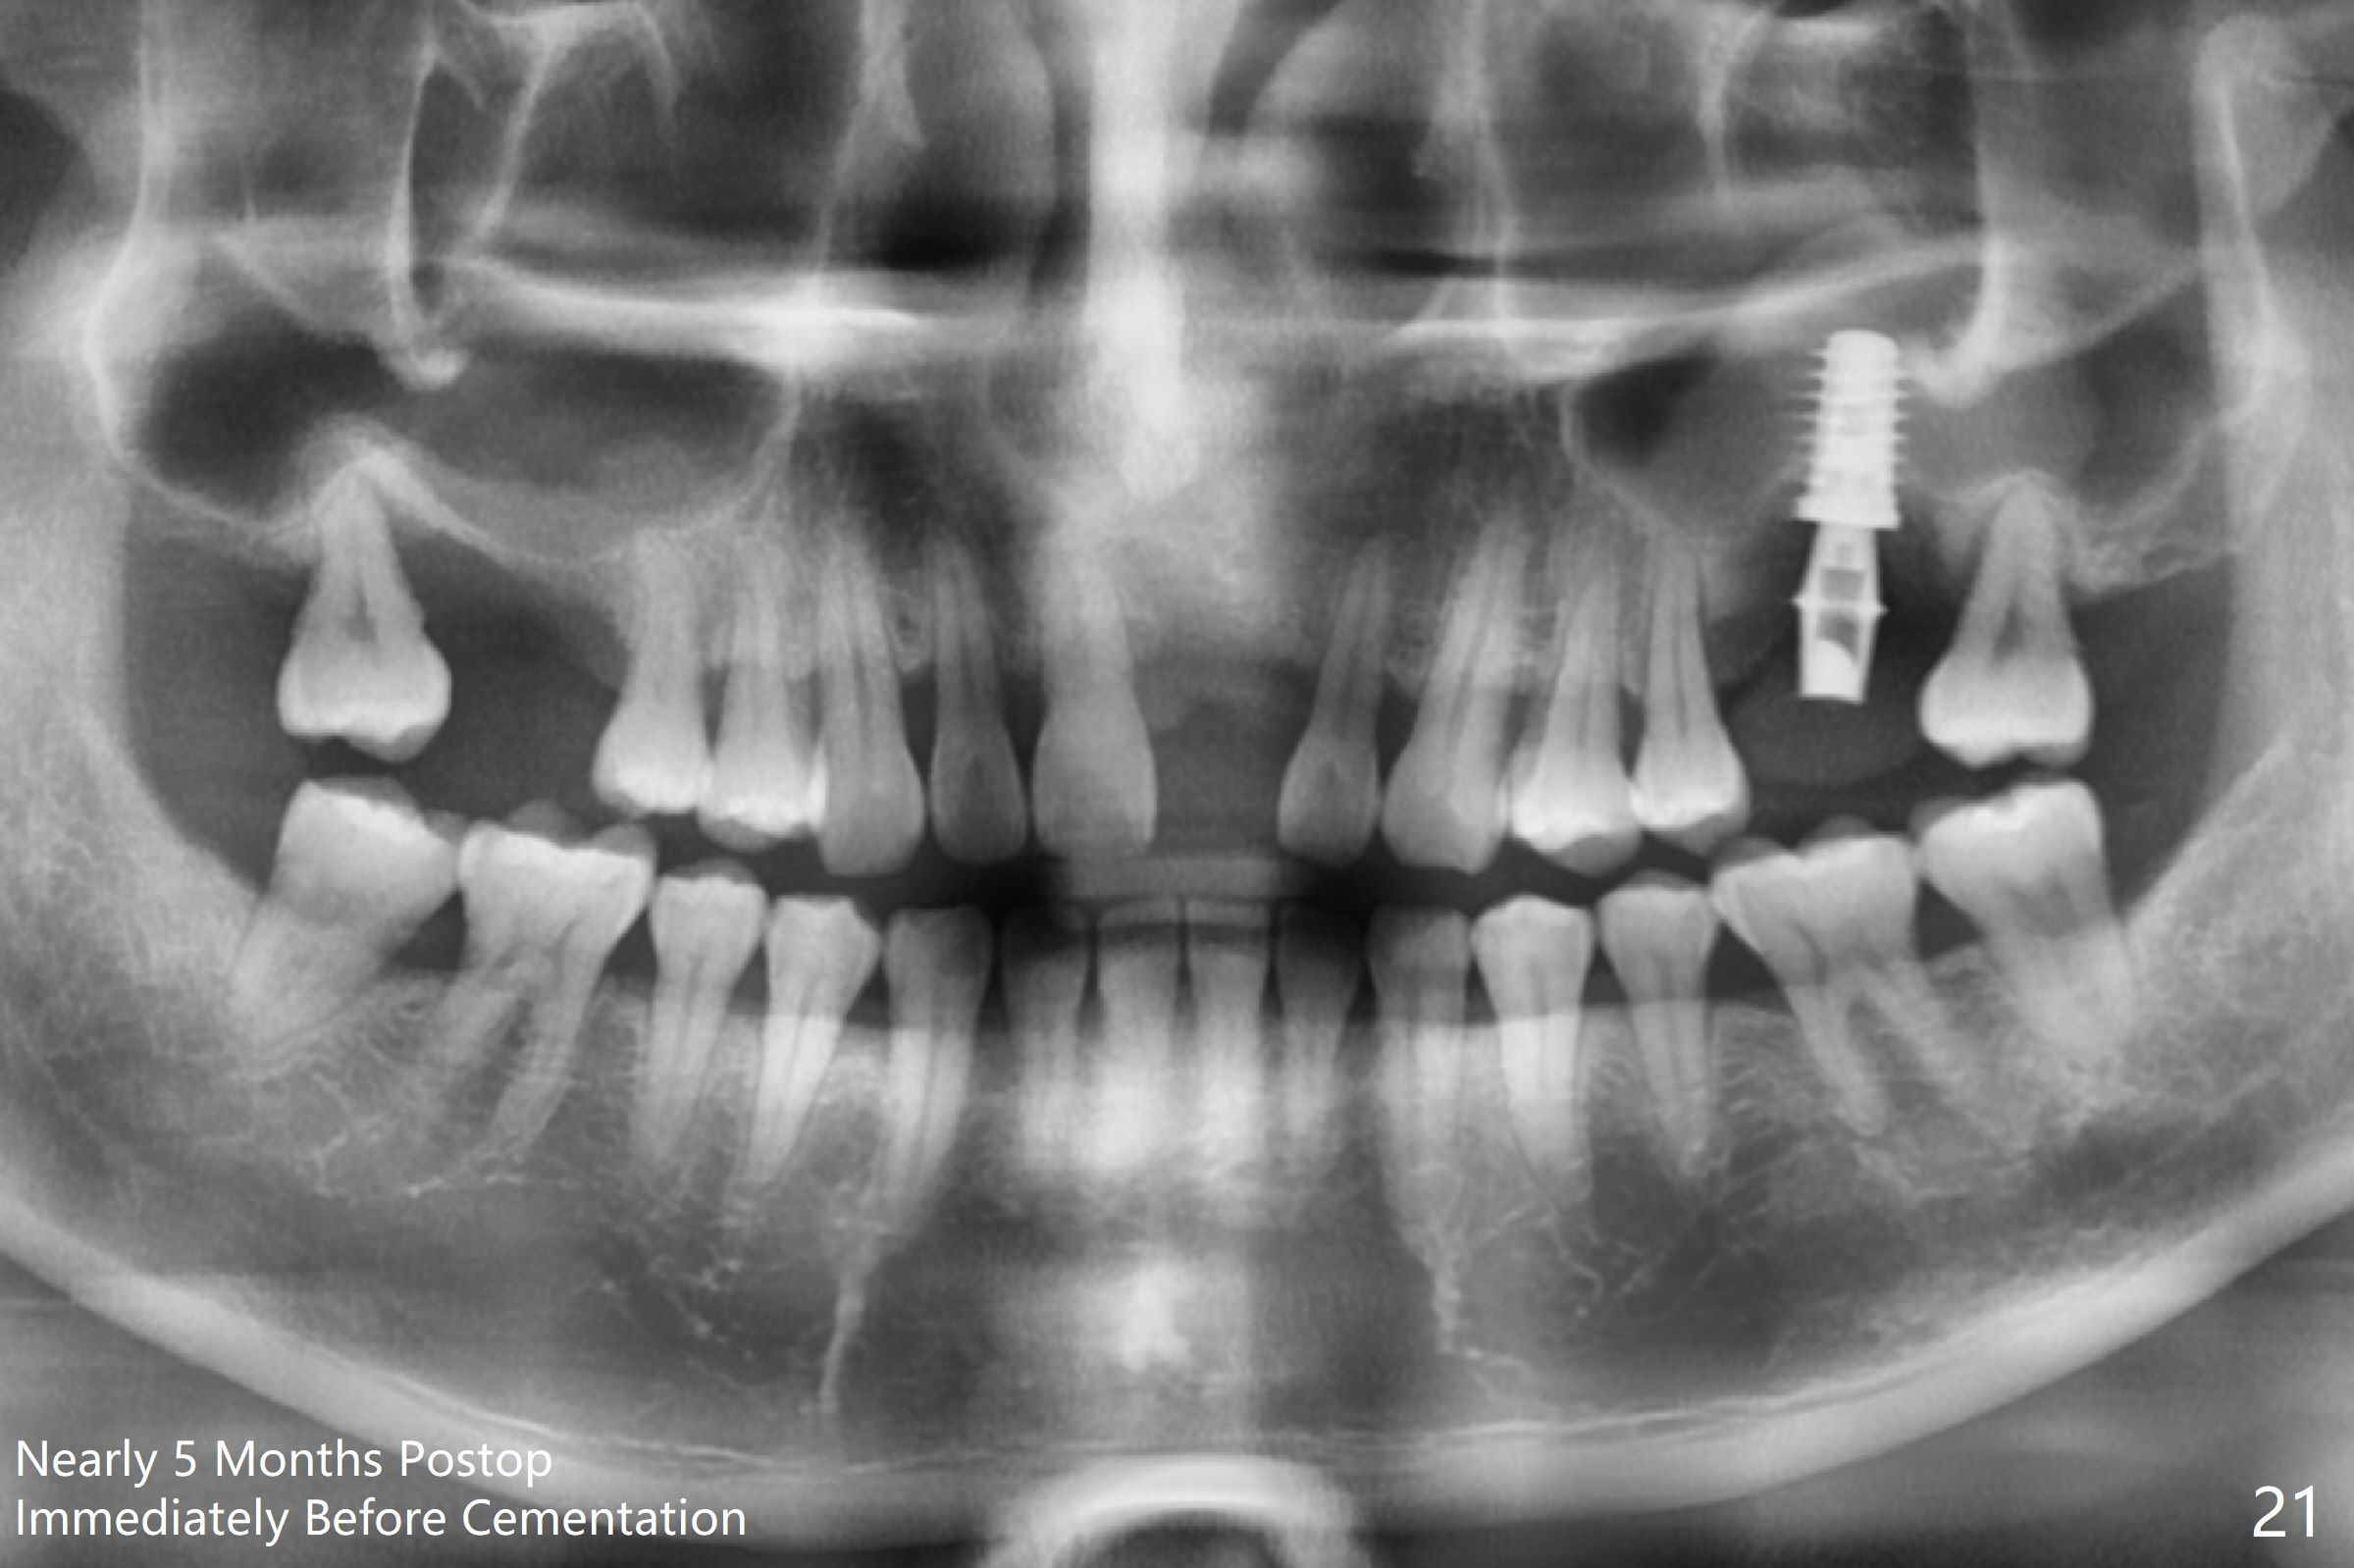

In fact, there is no coronal bone for the implant to be backed up.  Therefore, impression is taken after uncover and insertion of a 5.5x5.7(4) mm abutment.

There is a mushroom around the implant nearly 5 months postop/immediately before cementation (Fig.21).  The bone density around the implant is low (Fig.22-24' *).